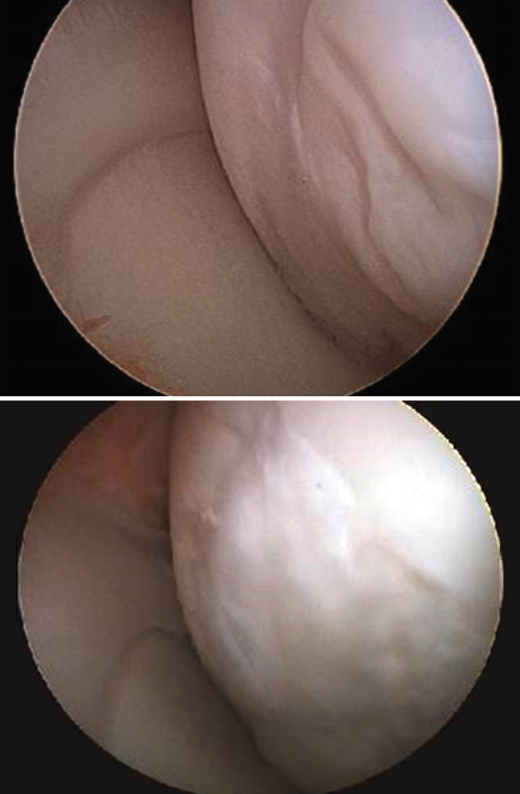

Figure 3. Outerbridge grading of joint cartilage lesions.

Although there are a number of classifications for assessing the degree of joint cartilage damage, the most widely used option is the classification of Outerbridge (1961), which defines four grades(5,6)(Figure 3):

• Grade I: softening or edema of the cartilage surface.

• Grade II: fissures or fragmentation affecting a surface of less than 1.25 cm in diameter.

• Grade III: fissures or fragmentation affecting a surface of over 1.25 cm in diameter.

• Grade IV: erosion of the cartilage extending to the subchondral bone.

Figure 4. Arthroscopic views of the Outerbridge chondral lesion grades. A: grade I lesion; B: grade II lesion; C: grade III lesion.

Figure 4 shows arthroscopic images of lesions corresponding to grade II (Figure 4A), grade III (Figure 4B) and grade IV (Figure 4C).